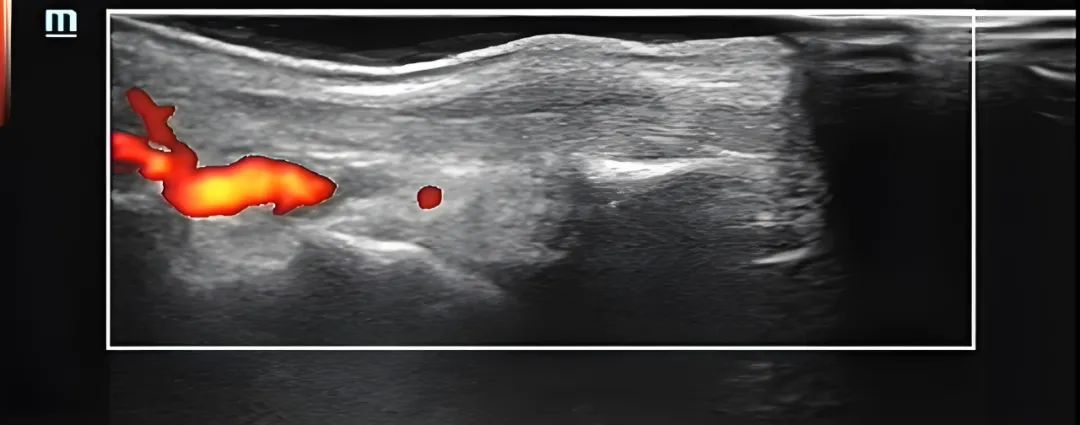

▲术中(可视化注射镇痛复合液)